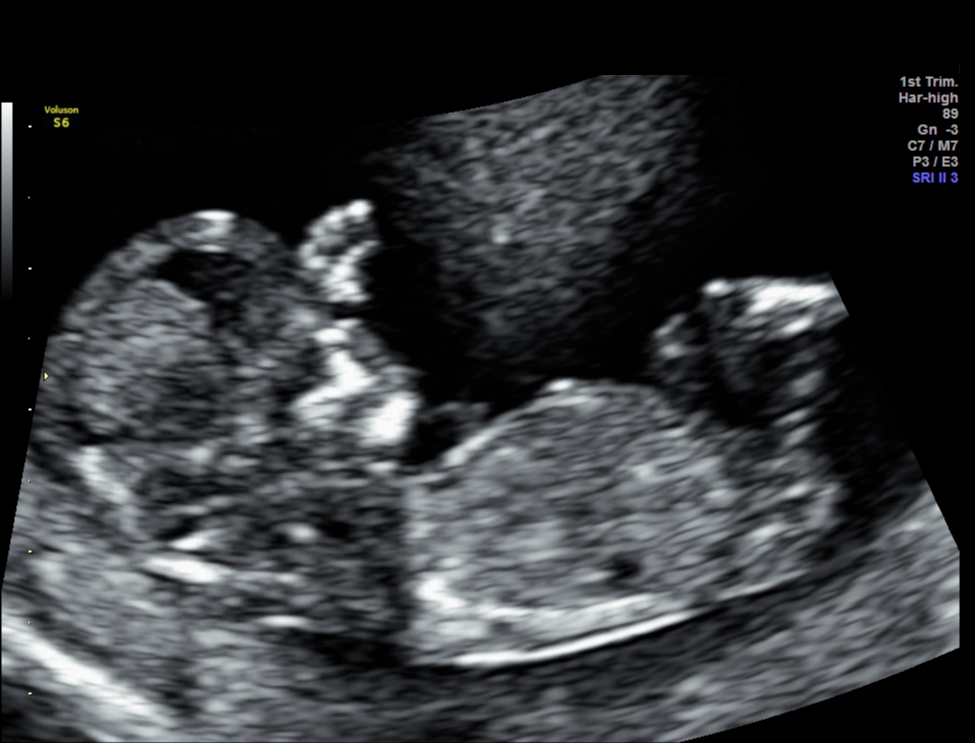

Attachment 33526Attachment 33527

HI everyone, This is my 1st post in this forum after reading many threads about gender predictions and some of you ladies are very knowledgable. These are my NT scan pics for today.

One picture I asked tech what the gender is and she said she was very unsure but it might develop to girl part. What do you guys think? I googled some boys potty shot also has three lines and why mine is protruding ???